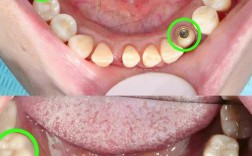

(图片来源网络,侵删)- 纯钛: 目前最主流、应用最广泛的材料,生物相容性极佳(与人体组织相容性好,不易引起排异反应),强度高,耐腐蚀性好,常用的是四级钛(纯度>99.9%),其强度和韧性最佳。